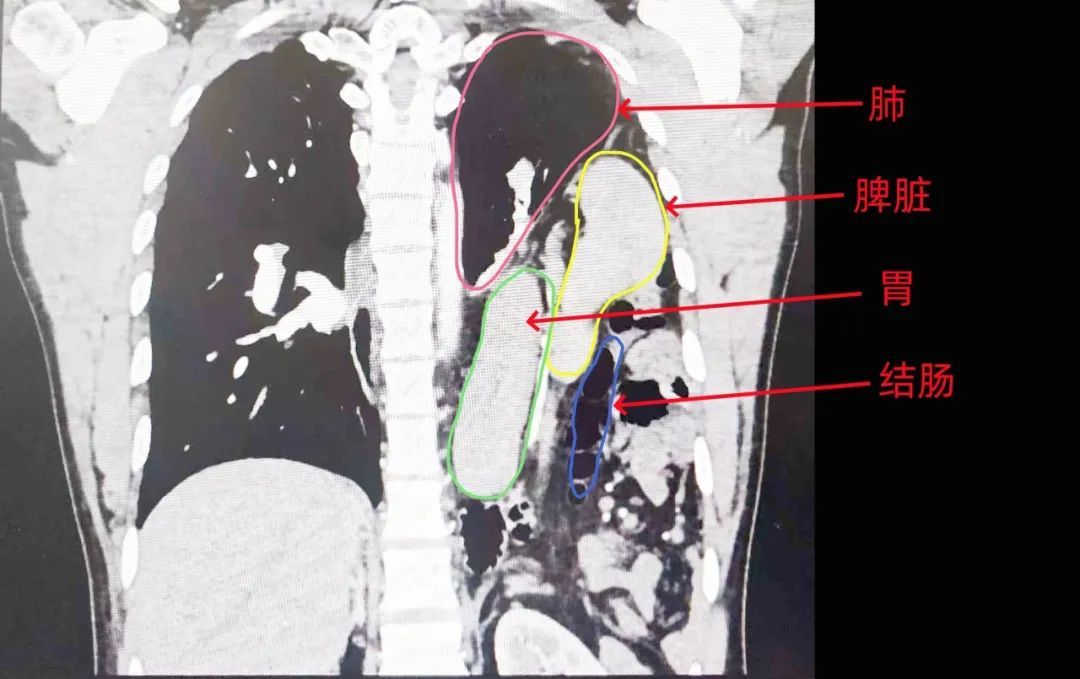

王先生腹腔内的脏器大量挤入胸腔,导致心脏、左肺受到严重压迫,左侧膈疝!

市民王先生的医学检查影像

很显然

王先生的脾胃肠

已经全部乱入到了胸腔里

手术开始后,医生们先用胸腔镜进行探查。果然,王先生的腹部器官几乎都“跑路”了,整个脾脏、胃、大网膜、结肠大部分都疝入了胸腔,与胸腔膈肌紧密粘连,情况比想象中复杂。

此外,医生们还不出意外地在王先生的左侧膈肌上发现了一个8-10厘米的裂孔,这就是王先生腹部内脏跑路的通道。